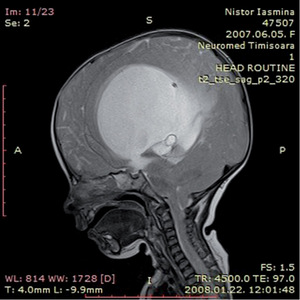

3.6.1. Hydrocephalus (59–63. ábra)

- Koponya-MRI: kamrák mérete– a fentiek, valamint occlusiót okozó eltérés kimutatása,sagittalis képeken a III. kamra fenekének lenyomottsága,aqueductus stenosis kimutatása.